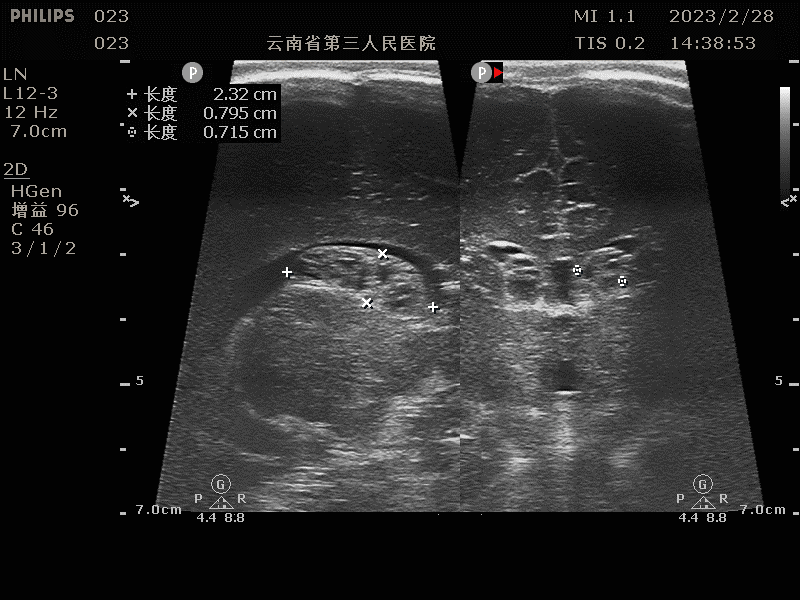

3. 脑积水:

脑积水是新生儿常见的颅内病变之一,超声检查可以准确评估脑室的大小和形态。

(室管膜下出血部分囊变声像)

(脑积水声像)